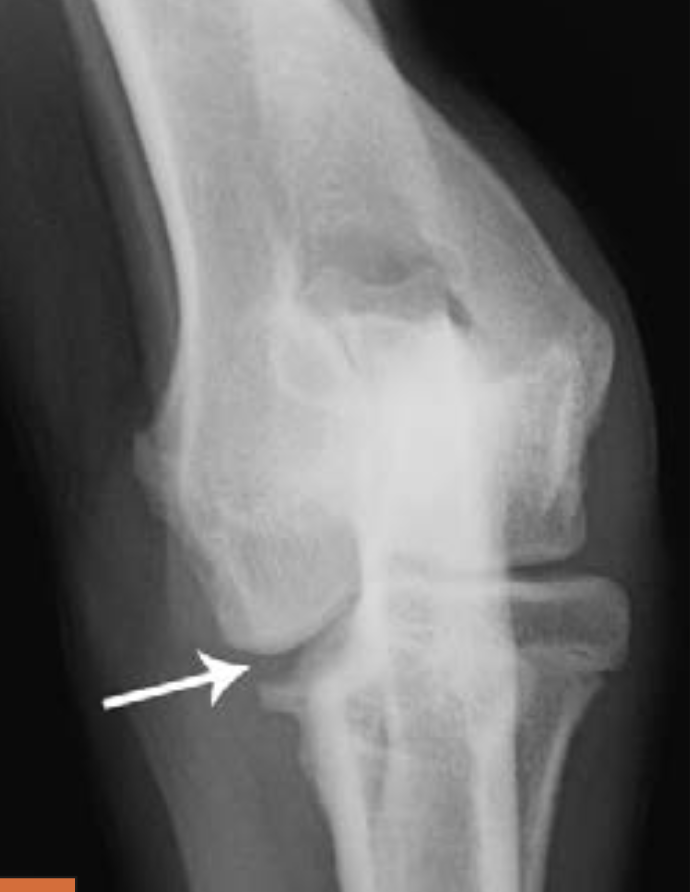

4-year-old Rottweiler

large separate medial coronoid fragment superimposed on the cranial radius (arrowed). Osteophytic reactions are seen on the cranial margins of the joint and on the anconeal process and subtrochlear sclerosis.